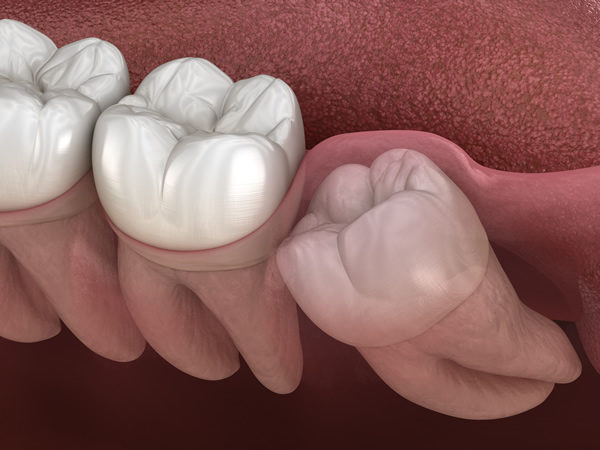

親知らずの抜歯は、歯の生え方や位置によって難易度が大きく異なります。

特に、歯ぐきの中に埋まっている「埋伏歯(まいふくし)」の場合は、通常の抜歯よりも高い技術と十分な処置時間が必要となります。

当院では、このような難易度の高い親知らずの抜歯にも対応しています。経験豊富な歯科医師が、痛みをできる限り抑えながら、短時間かつ安全性に配慮した処置を行います。

親知らずを抜くべきかどうかの判断基準は、「生え方」にあります。基本的には、斜めや横向きなど、まっすぐ生えていない親知らずは抜歯を推奨しています。

横向きに生えている「水平埋伏歯」は、手前の歯を圧迫し、痛みや歯並びの乱れ、虫歯・歯周病の原因となることがあります。